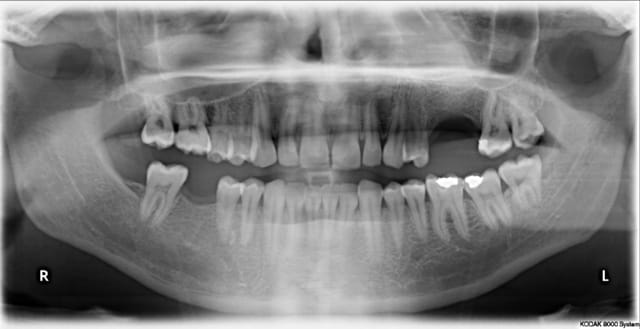

Patient 26 ans, à qui il manque 46, 25 et 26.

Pour l'instant je vous propose la partie préparation et mise en place de l'implant en 46, la suite peut être bientôt.

Dans l'ordre si le site veut bien, wax-up ( cirage pour céramik ;) ) , guide radio, et scan.

Photos pré-op, indicateur de direction en place et post-op.

Il s'agit d'un implant astra osseospeed de 5 mm de diamètre et 9 de long.

Prothèse prévue à 6 semaines.

puisque tu veux de la critique, impec (juste que je l'aurais mis à peine, mais vraiment à peine moins infra-osseux)

c'est à cause du profil de la crête, en fait l'implant est juxta-osseux en vestibulaire, par contre moi je le trouve ( légèrement ) trop distal.